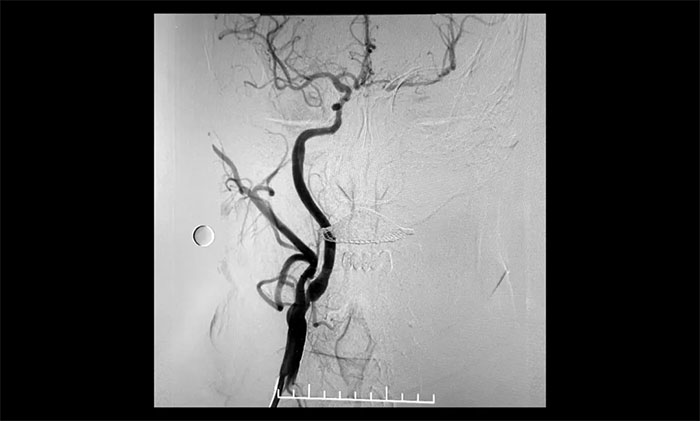

▲ 术后,右颈内动脉起始段狭窄明显改善

▲术后,左颈内动脉起始段狭窄明显改善,左颈内动脉颅内段顺利再通,左颈内动脉眼动脉段、后交通段狭窄明显改善

经微导丝成功进入狭窄、闭塞颈内动脉,在支架保护下,进行球囊逐段扩张,支架置入……,经多次球囊扩张,置入支架后,造影显示左颈内动脉起始段狭窄明显改善,左颈内动脉颅内段顺利再通,左颈内动脉眼动脉段、后交通段狭窄明显改善。造影及3D造影见左颈总动脉、左颈内动脉、左大脑中动脉显影可,行支架CT见颅内支架成形可,手术取得成功!

术后,患者生命体征平稳,无新发神经功能障碍。术后,患者言语不利、肢体活动不利等症状明显好转。